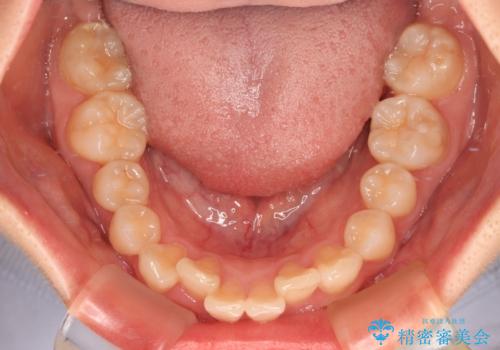

- 上下前歯のデコボコを気にして来院された患者様です。

マウスピースでもワイヤー装置でも対応可能でしたが、右側の咬み合わせが上顎がやや前方に位置していることから、補助装置を使用することが推奨されました。

自己管理の煩わしさを気にして、補助装置併用によるワイヤー装置での矯正治療を行うこととしました。